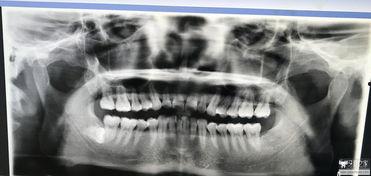

在正式开始正畸之前,医生会为你进行一系列的检查,包括口腔X光片、牙齿模型等。这些检查可以帮助医生了解你的牙齿状况,制定合适的治疗方案。同时,医生还会告诉你正畸过程中需要注意的事项,比如保持口腔卫生、避免过硬食物等。